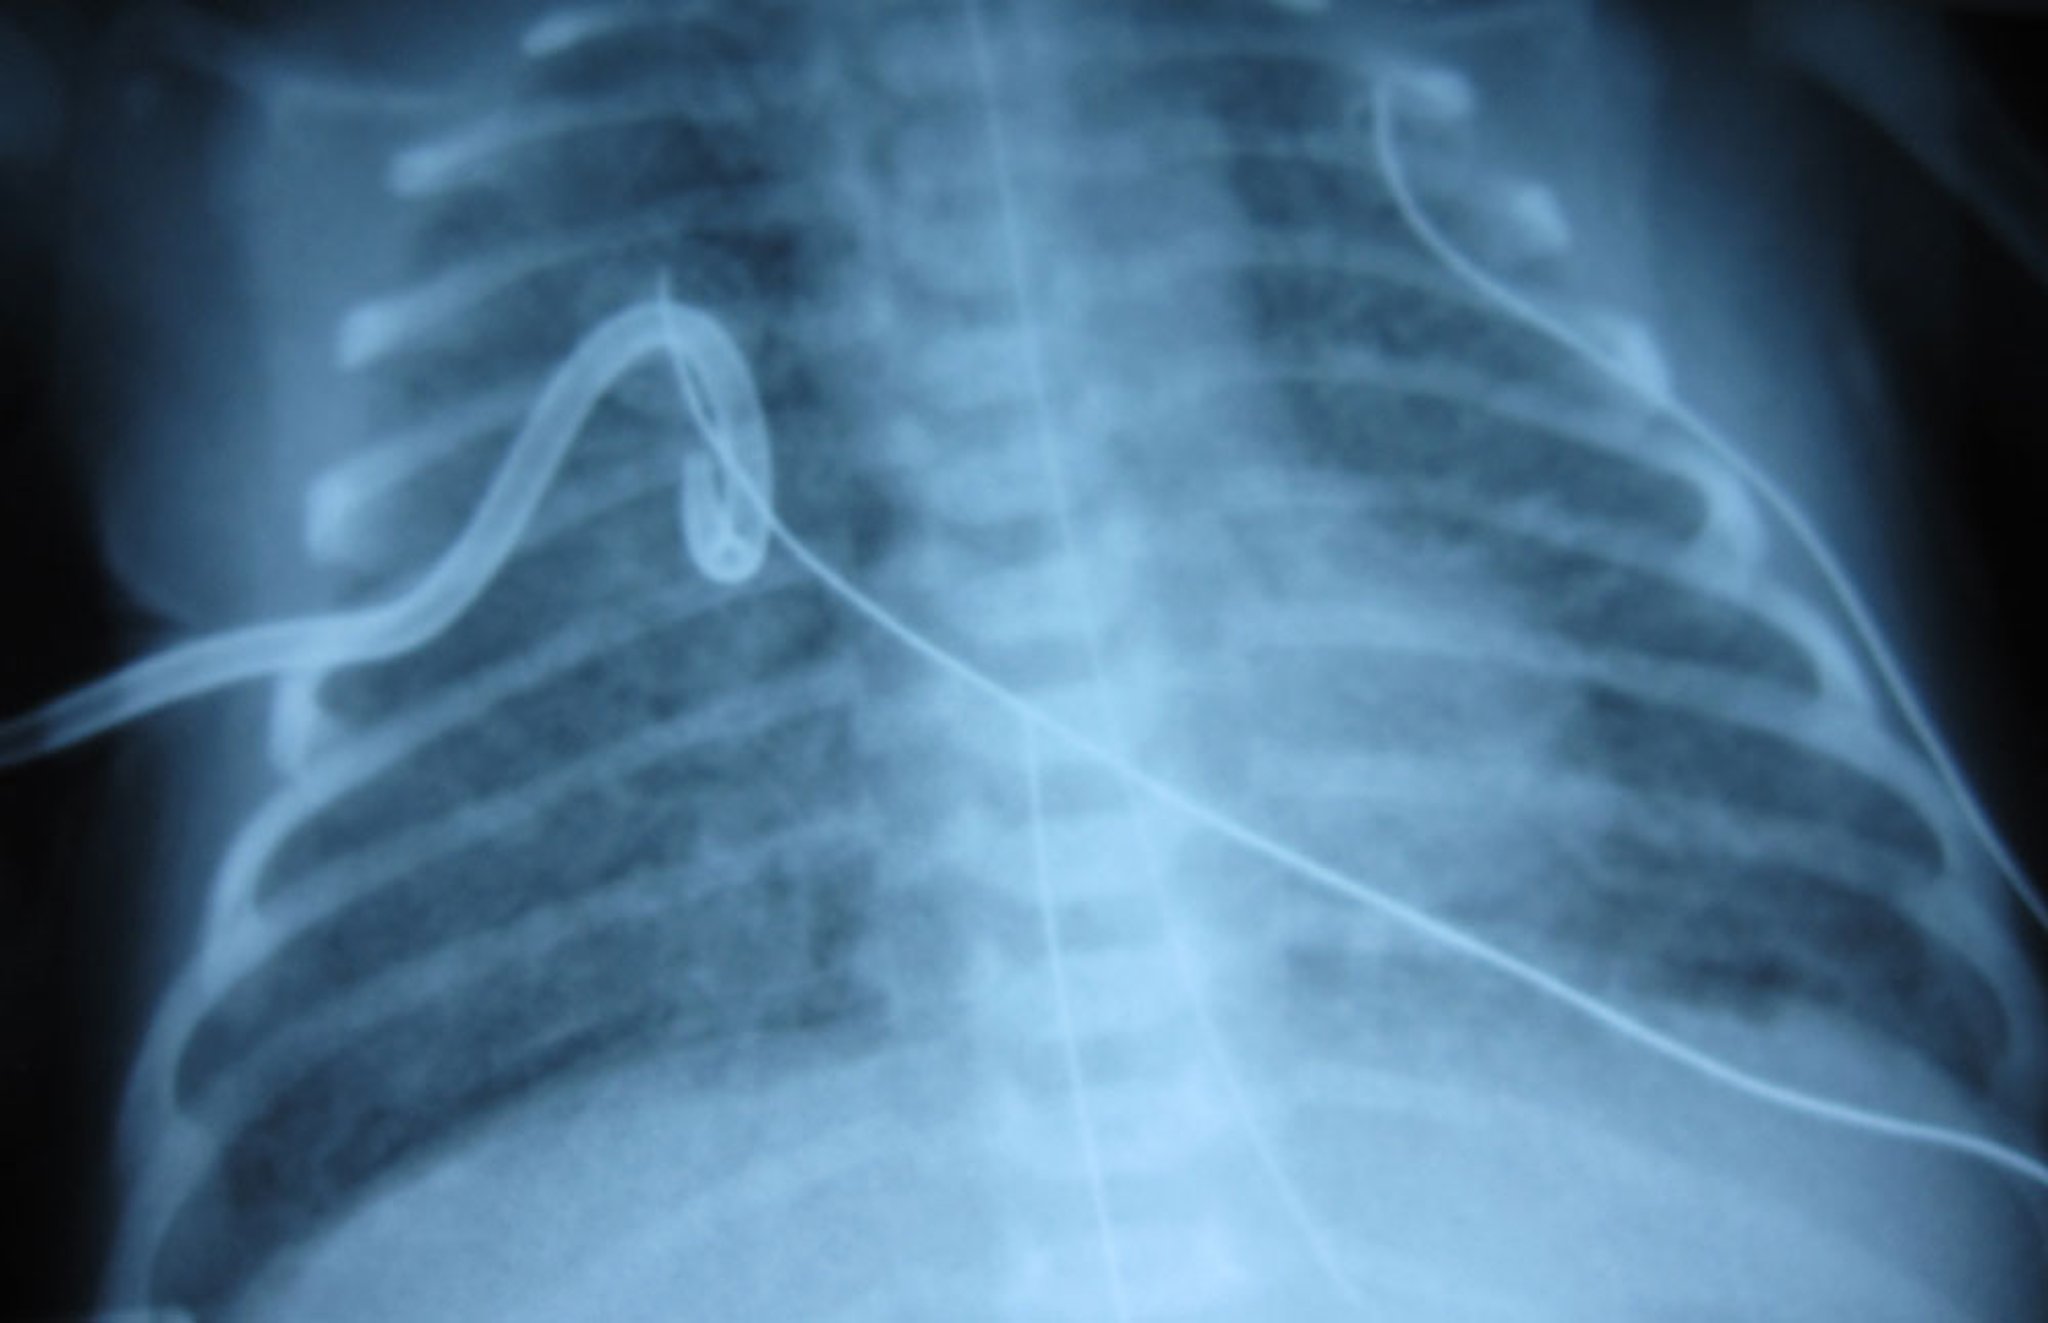

置入胸管后的气胸

图示右肺在置入猪尾胸管后再次扩张,清晰可见肺纹理。

肺水肿是先天性心脏病所致(肺静脉回流完全异常),与气胸无直接关系。